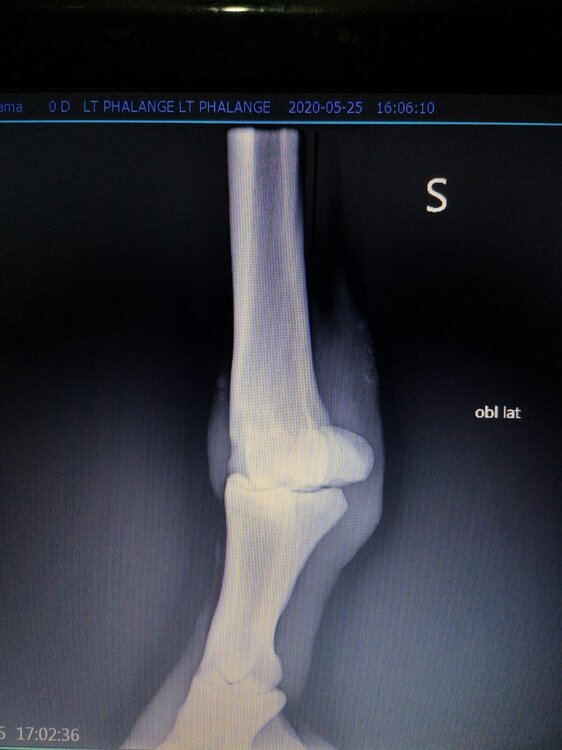

Salve volevo chiedervi qualche informazione in merce tò a un problema che ho avuto con la mia puledra. Qualche settimana fa mentre stavo lavorando alla corda è scivolata urtato l'arto posteriore sinistro. Arrivati in box ho messo dell'acqua a pressione perché si era gonfiato sia il nodello sia il pastorale. Già l'indomani l'arto era sgonfio ritornato normale, quindi ho continuato a lavorarla. Ma dopo qualche giorno di lavoro alla corda leggerissimo, al rientro in box ho notato che sia il nodello che il posturale gonfiavano nuovamente. Allora ho chiamato il veterinario che ha detto che la cavalla aveva una lussazione e mi ha insegnato come cura una fasciatura con della creta per 24h per cinque giorni e un antinfiammatorio. Dopo un paio di giorni la fasciatura ha fatto come delle vesciche e il gonfiore è aumentato dal pastorale alla garra. Abbiamo chiamato un altro veterinario abbiamo fatto vedere anche a lui la cavalla e diceva che poteva essere la frattura del ditino, ma si dovevano fare le lastre per essere sicuri. Ora abbiamo fatto le lastre e il radiologo dice che c'è dell'infiammazione ma non c'è niente di grave. Il veterinario,viste le lastre dice che deve essere operata. Allora abbiamo consultato un'altro veterinario che dice che la cavalla non ha assolutamente niente. Ora io vi allego le radiografie, datemi un vostro parere perché non só più cosa fare. Grazie